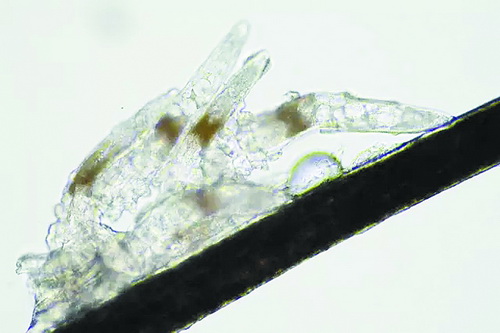

顯微鏡下長(zhǎng)在睫毛中的螨蟲(chóng)

冬天來(lái)了,氣溫降低,睫毛上的“隱形殺手”蠕形螨卻沒(méi)有要冬眠的意思。廈門(mén)大學(xué)附屬?gòu)B門(mén)眼科中心11月初開(kāi)設(shè)蠕蟲(chóng)性瞼緣炎門(mén)診以來(lái),每天來(lái)查螨的市民都特別多,短短一個(gè)多月,已有近千人在顯微鏡下見(jiàn)到長(zhǎng)期寄居在自己睫毛上,朝夕相處,卻素未謀面的蠕形螨。